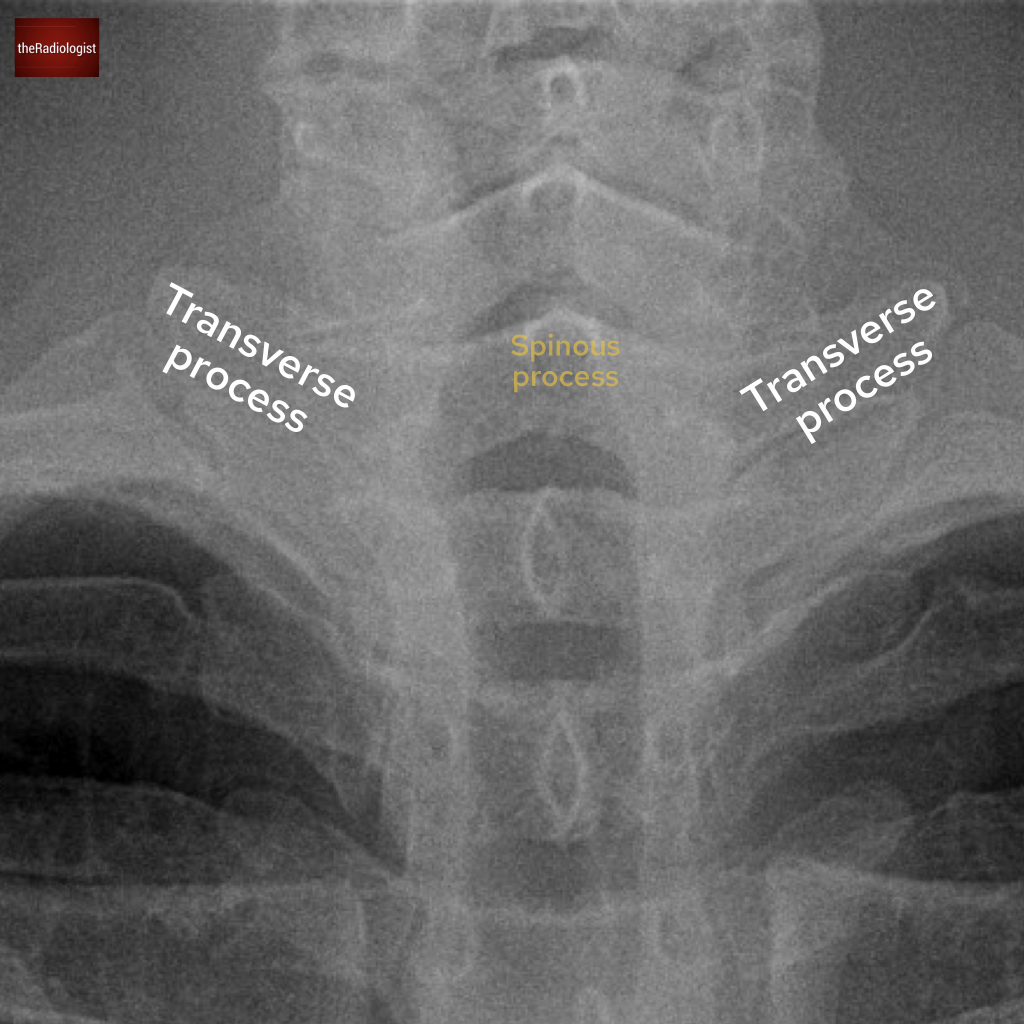

Let’s start with a PA chest X-Ray. What is the arrow pointing at?

Choose one from the following options: